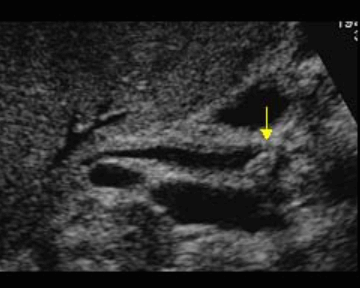

미리찌 증후군 (Mirizzi's syndrom) Mirizzi's syndrom 은 담낭경부, Hartmann's pouch 혹은 담낭관의 결석에 의해 총 간관(CHD)이 폐쇄되는 질환이다. 총 간관(CHD)이 협착되면서 상부담관은 확장되고 하부담관의 직경은 정상으로 나타난다. 증상은 폐쇄성 황달, 복부통증, 발열 등이 나타난다. 급성담낭염이 있으면서 담관폐쇄를 동반할 경우 의심해 볼 수 있다. 담낭절제술 후에 남아있는 담낭관의 결석이 총 간관(CHD)을 직접 누르거나 염증성 협착을 유발하기도 한다.

US finding

- 담낭관 또는 담낭 경부에 결석이 확인된다.

- 총간관(CHD) 또는 담낭관(cystic duct)의 확장소견이 보인다.

- 간내외 담관의 확장이 관찰된다.